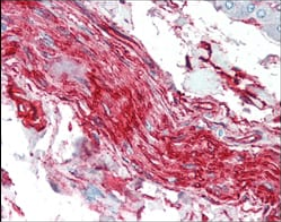

IHC    1/200 - 1/1000